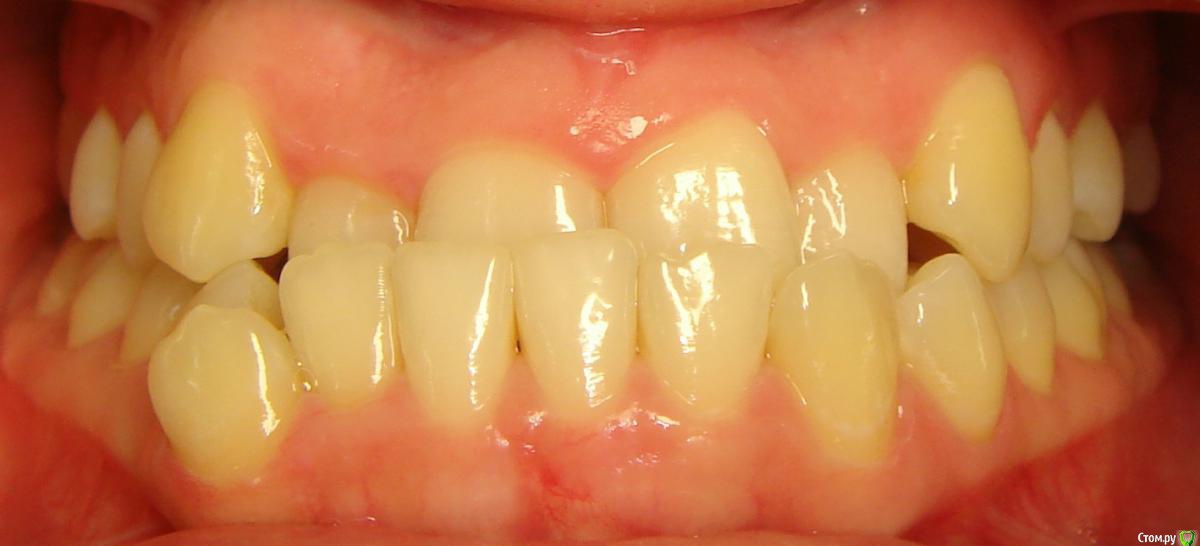

Opdihatop Опубликовано 10 декабря, 2016 Поделиться Опубликовано 10 декабря, 2016 Добрый вечер, коллеги! У меня вопрос к тем, у кого опыта по MEAW больше, чем у меня. Пациентка, 24 года, на данный момент все зубы мудрости удалены, привычная окклюзия по резцам - край в край. Сам процесс я понимаю, но есть несколько нюансов, которые хотелось бы уточнить:1) Нивелировать ли просто фронт в/ч, как книжка пишет (просто поставить дугу и все), или все-таки немного дистализировать боковые участки? С одной стороны простое нивелирование ускорит процесс и облегчит перебрасывание резцов, с другой стороны я опасаюсь чрезмерной протрузии из-за выравнивания дистопированных клыков; но при этом дистализация усугубит 3-й класс.2)Какой высоты делать окклюзионные накладки, в книжке они минимальные, а мне как то хочется побольше, чтобы резцы разомкнуть почти край в край, но не испортит ли это биомеханику?Буду очень благодарен вам за помощь! Ссылка на комментарий